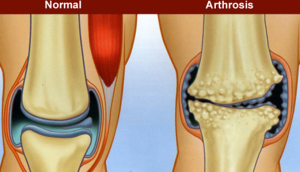

Halk arasında kireçlenme olarak bilinen hastalık ya da tıbbi adı ile “artroz” veya “osteoartrit” eklemlerde meydana gelen aşınma ve yıpranma sonucu ortaya çıkar. Kemiklerimizi birbirine bağlayan eklemlerimizde, karşılıklı kemik yüzeyleri üzerini kaplayan ve ağrısız ve kaygan hareketi sağlayan eklem kıkırdağı bulunur. Yıllar içinde bu parlak ve düzgün yüzeyli doku aşınır, eskir ve yer yer dökülerek altındaki kemik ortaya çıkar. Yaygın inanışın aksine, artrozda eklemlerde kireç birikmesi söz konusu değildir.Artroz en sık yük taşıyan eklemlerde görülür. En fazla diz eklemi olmak üzere, kalça, el parmakları ve omurga sık olarak tutulur. Buna karşın, özel bir yaralanma olmadığı müddetçe bilek, omuz, dirsek gibi eklemlerin tutulumu nadirdir.

Artrozun en önemli bulgusu ağrıdır. Önceleri eklemi kullanmakla artıp dinlenmekle geçen ağrılar, hastalık ilerledikçe kalıcı hala gelebilir. Eklemlerde şişlik, kemik çıkıntılar ve şekil bozuklukları ortaya çıkar. Kemik yüzeylerin birbirine sürtünmesi sonucu kıtırtı şeklinde sesler duyulabilir. Eklemlerin hareket açıklığı azalır ve tutulan eklemde işlev kaybı ortaya çıkar. Hareketin başlangıcında ağrı ve eklem sertliği daha fazladır. Hareket tekrar tekrar yapıldığında sertlikte bir miktar düzelme olur. Bu araba motorunun ısındıktan sonra daha iyi çalışmasına benzetilmiştir. Hastaların yakınmaları soğuk ve nemli havalarda daha da artar.

Diz eklemindeki en önemli belirti ağrıdır. Bunun dışında hareket kısıtlılığı, eklem sıvısının artmasına bağlı şişme, eklem çevresi kasların incelmesi ve diz eklemindeki aşınmaya bağlı olarak şekil bozukluğu görülebilir. Zaman içinde diz deforme olarak bacaklar içe doğru eğrilir. Eklem içinde serbest gezen kıkırdak veya kemik parçalarına bağlı olarak dizde takılma ve kilitlenme gibi belirtiler ortaya çıkabilir.